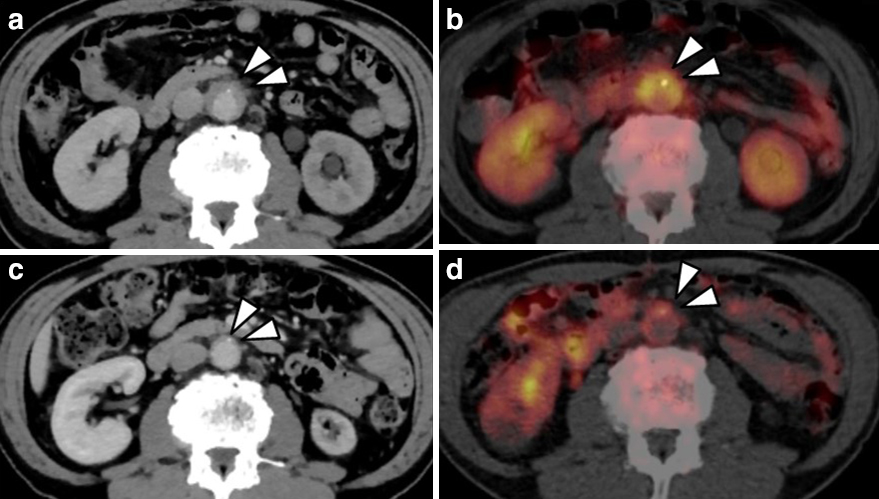

PET-CT所見:直腸癌にstandardized uptake value(以下,SUVと略記)max 13.3,左総腸骨動脈周囲軟部陰影にSUVmax 5.5,右総腸骨動脈周囲軟部陰影にSUVmax 4.2の18F-FDGの異常集積を認めた(Fig. 2b矢頭).腹部大動脈周囲の軟部陰影にもSUVmax 5.5の18F-FDGの異常集積を認めた(Fig. 3a矢頭,3b矢頭).

a: Preoperative contrast-enhanced CT. b: Preoperative PET-CT. c: Postoperative contrast-enhanced CT. d: Postoperative PET-CT. Before the operation, soft masses were found peripheral to the abdominal aorta, and FDG accumulation was found peripheral to the abdominal aorta. After surgery, the retroperitoneal soft masses and FDG accumulation improved.

術後経過:経過良好で,術後第8病日に尿管ステントを抜去し,術後第10病日で退院となった.後腹膜線維症に関しては術後にステロイドを投与することなく経過観察のみで下腿浮腫は術後1か月で改善した.術後4か月目のCTでは腹部大動脈周囲の後腹膜軟部陰影の改善(Fig. 3c矢頭),および術後8か月目のPET-CTでは,18F-FDG異常集積の改善が認められた(Fig. 3d矢頭).術後6か月目にはCre 1.43 mg/dl,術後16か月目にはCre 1.11 mg/dlまで腎機能は改善した.術後31か月現在,無再発生存中である.